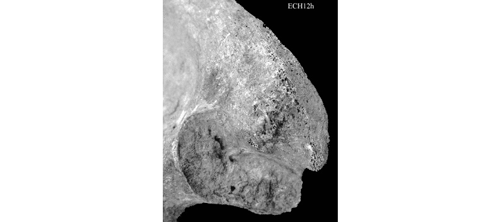

SSPIC (Modification Apicale)

L’apex est le bord de la surface articulaire, à la jonction des deux segments. Les changements sont de type enthésopathies.